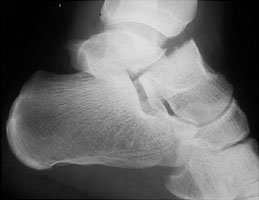

B | Mortise radiograph of the ankle. This better shows the involvement of the fracture. |